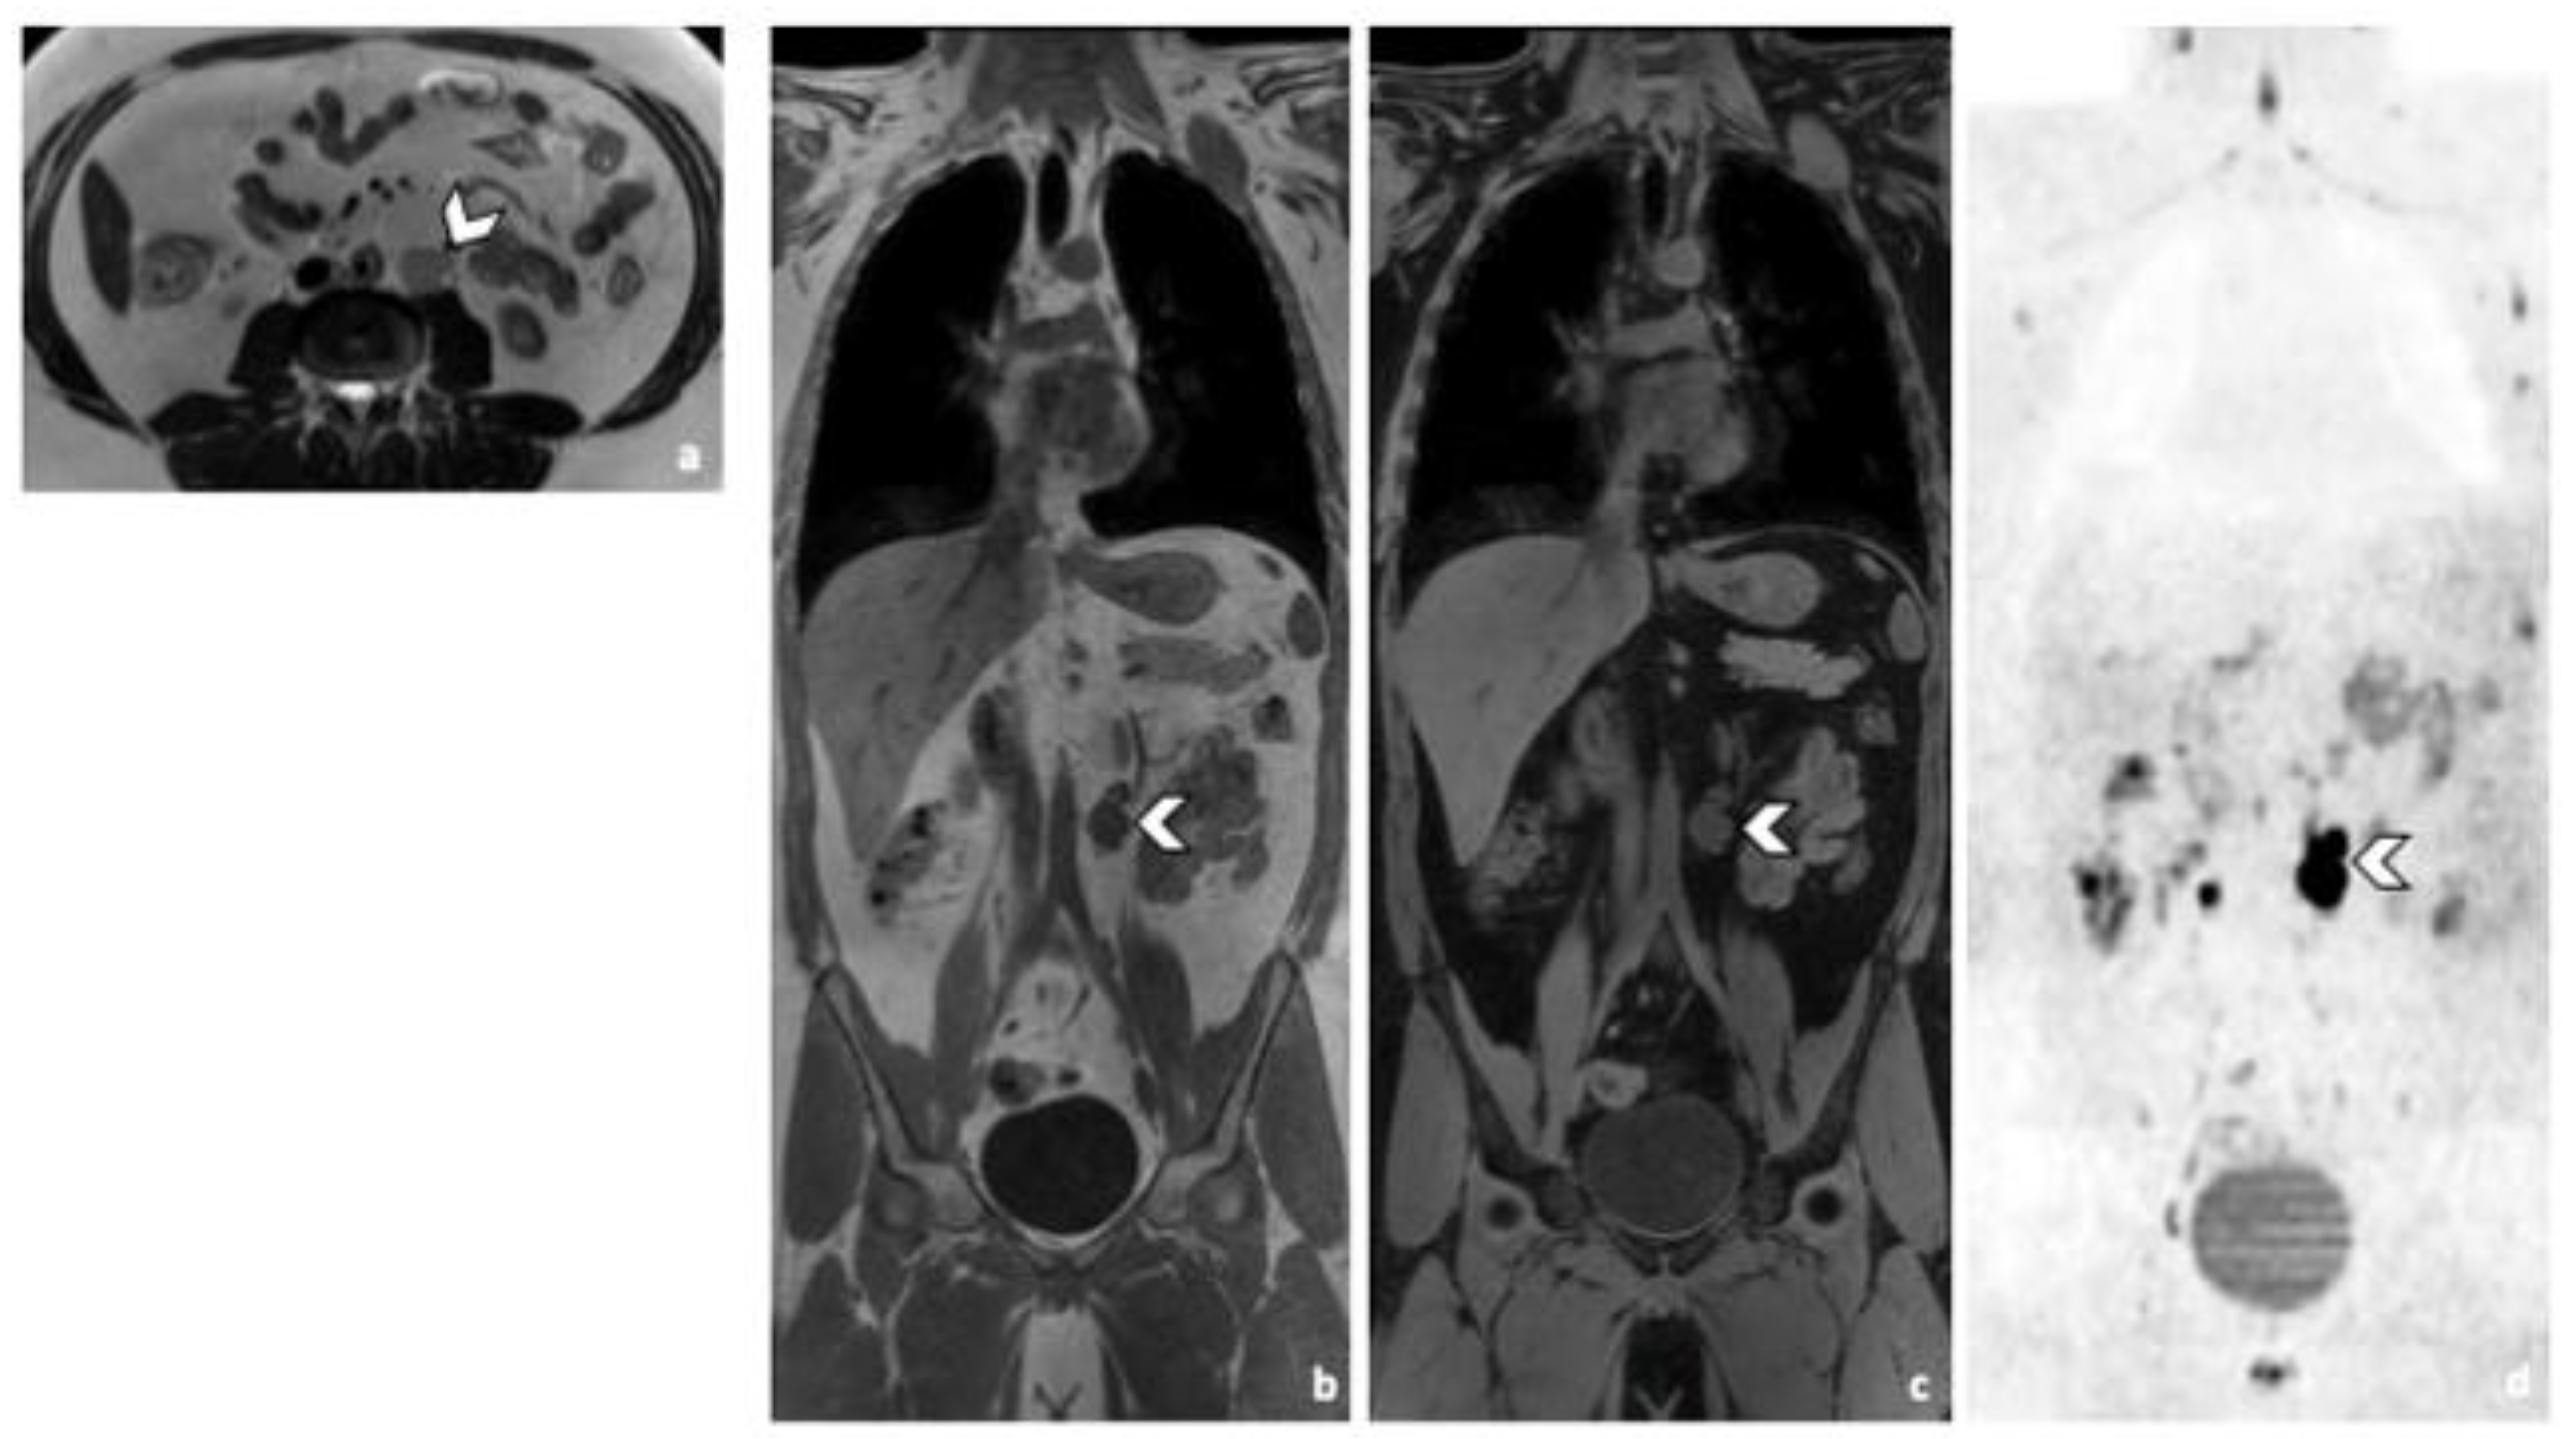

Figure 2.

Comparison of WB sequences in a 30-year-old patient with seminoma. Axial T2-weighted (a) and coronal reformatted 3D T1 GRE In Phase (b), 3D T1 GRE Fat Sat (c) and high b-value DWI (inverted greyscale, b = 1000 s/mm2) MR images of the whole body (d). Detection of an enlarged pathological para-aortic lymph node (arrowhead) demonstrating an intermediate signal intensity in T2 (a), a hypointense homogenous signal in T1 (b,c) and a restricted Diffusion (d). In this case, each sequence clearly depicted the retroperitoneal lymph node. Abbreviations: 3D: Three Dimensional, T1 GRE: T1 Gradient Echo, DWI: Diffusion Weighted Imaging.